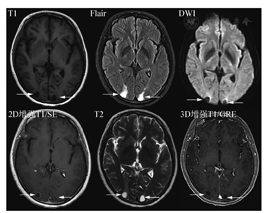

最低标准中,核心是强调了薄层扫描。3D是各向同性块扫描,重建后的单层图像可达到1mm或者0.6mm薄层厚度。共识建议3D扫描,如果不能进行3D扫描,2D扫描层厚要求是3mm;在序列选择方面,首选SE序列。SE是经典MRI序列,病灶显示度高,但扫描时间略长。如果不能进行增强后3DSE序列扫描而使用了3DGRE序列扫描(优点是快,缺点是由于白质信号增高而导致病灶对比度不够,皮质浅表病灶显示差,由于不能附加压脂导致颅骨转移瘤显示差,以及亮血效应带来的脑沟内血管过度显示),建议增加一个增强后2DSE序列。各序列实例比较见图2。

另外,DWI由于非常有诊断价值和扫描时间短,建议始终放在平扫序列里。而注射造影剂前的平扫中,只扫Flair序列,T2放在增强后扫描。优化标准中,主要增加了DSC灌注扫描(可能对鉴别肿瘤复发和放射性坏死有用)、增强后Flair(显示软脑膜转移病变较常规增强T1MRI效果好)以及增强后长时间延迟扫描(60~105 min,以期显示小病灶)。关于增强后Flair序列,对于脑膜转移的增强显示能力已被认可。对于脑实质内的转移瘤病灶,并不能增加诊断信息,但是对于靠近皮质的表浅病灶,显示能力超过常规增强T1,详见图3、图4。不同MR扫描机的序列名称不同,但序列的本质一致。